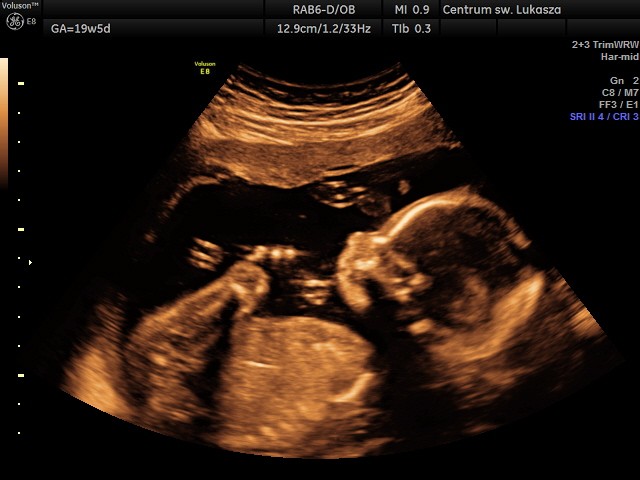

Chciałam się też pochwalić, że chyba jako pierwsza październikowa mama, miałam wczoraj USG połówkowe. Wymarzony chłopak machał klejnotami na lewo i prawo

Wszystkie parametry w porządku. Waga 320 gram.